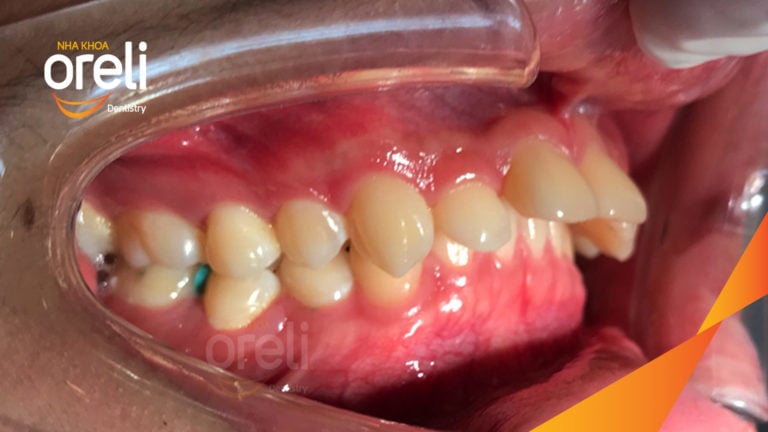

Niềng răng lệch khớp cắn tại Buôn Ma Thuột – Hành trình thay đổi nụ cười tại Nha khoa Oreli Niềng răngMóm Xem thêm